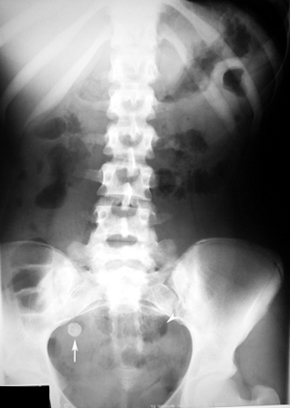

Appendicolith

Findings:

- Plain film showing appendicolith.

- Arrow points to ileus.

- Appendicolith may be seen without clinical signs of appendicitis.